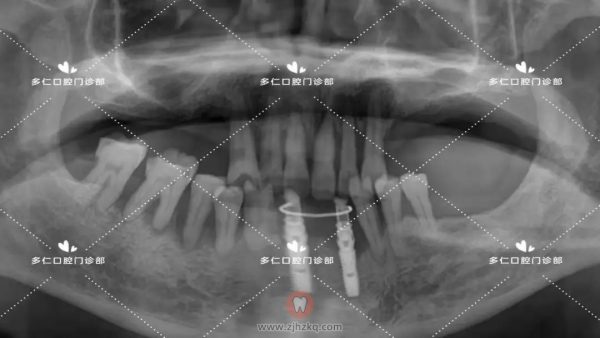

术后全景片照片如下